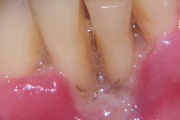

Suulaepoolt lõikunud koonilise kujuga lisahammas